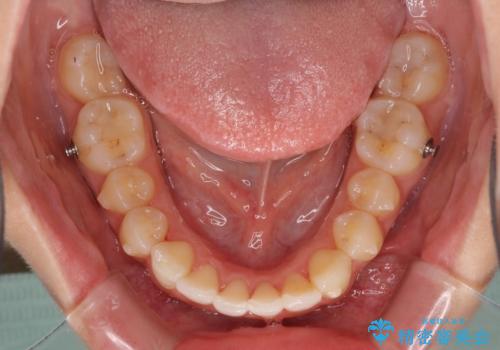

歯列全体の拡大とIPR(歯と歯の間を削る)によってデコボコが解消するようにし、さらにゴムかけを活用して右側の咬み合わせ位置を変えるように設計し、インビザラインにより治療を行うこととしました。

後方移動に際し、上下顎の親知らずは3本とも抜歯することとしました。

結婚式までに前歯を整えたいとのことでしたが、インビザラインでは先に奥歯を移動させてから前歯を動かすため、間に合わない可能性がありました。しかし、結婚式までに期間があったことと、マウスピースをしっかりと装着してくださったことで、十分な歯列に整えることができました。